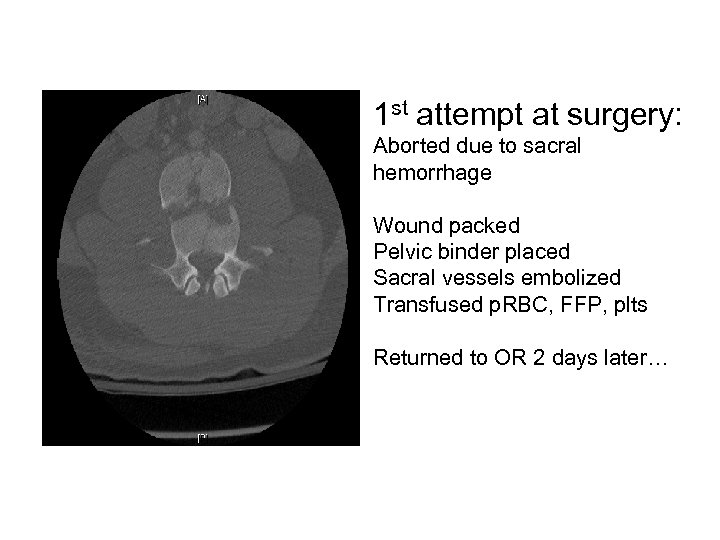

22 M motorcycle crash Motor - 2/5 hip flexion and knee extension - 0/5 below knee - diminished rectal tone Sensory - Diminished sensation to light touch below knee Reflexes - None at knees and patella - No clonus 3 rd degree instability TLICS 9 (3+3+3) ASIA C

1 st attempt at surgery: Aborted due to sacral hemorrhage Wound packed Pelvic binder placed Sacral vessels embolized Transfused p. RBC, FFP, plts Returned to OR 2 days later…

Post op result L 1 -L 5 segmental instrumentation and posterolateral fusion Correction of fracture-dislocation using Wilson frame and reduction screws Motor - unchanged Sensory - some ROF below knees Bracing - TLSO Follow up - 6 week repeat X rays Not yet

Teaching points • Fracture-dislocations lead to majority of neurologic deficits from spine traumas (~50%) • Recognize other trauma injuries • Many spine fractures are URGENT (treat within 48 hours). Very few are EMERGENT (treat < 12 hours). – Wait for hemodynamically stability AMAP • Know fracture pattern/ anatomy preop • Be prepared for other injuries (thecal sac/ nerve roots, vascular, ureters, bowel, etc)